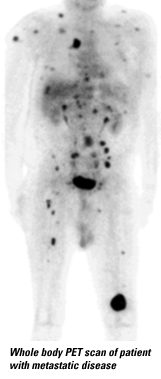

Esta imagem mostra um tumor cerebral. O PET é muito útil não apenas para detectar um tumor quando ele está em um estágio inicial de crescimento, fazendo com que o tratamento seja mais efetivo em radicá-lo, mas também para detectar o seu tipo, grau de malignidade, reespalhamento pelo corpo, sem a necessidade de abrir o cérebro do paciente para fazer uma biópsia arriscada. O PET agora está sendo usado pôr médicos para dar informações valiosas sobre muitas doenças neurológicas

Essas imagens, também feitas no Instituto Crump na UCLA, mostram o aumento da atividade cerebral que acompanha o crescimento do cérebro, no mesmo paciente, na idade de 01 até 12 meses. Isto pode ser usado, por exemplo, para detectar problemas de desenvolvimento em crianças, muito mais cedo do que outros testes conseguiriam. . Esta imagem mostra um tumor cerebral. O PET é muito útil não apenas para detectar um tumor quando ele está em um estágio inicial de crescimento, fazendo com que o tratamento seja mais efetivo em radicá-lo, mas também para detectar o seu tipo, grau de malignidade ,reespalhamento, pelo corpo, sem a necessidade de abrir o cérebro do paciente para fazer uma biópsia arriscada.